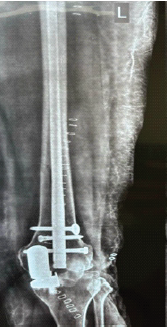

Rare Periprosthetic Fractures Following Oxford Unicompartmental Knee Arthroplasty: A Case Series of Supracondylar Femoral and Proximal Tibial Fractures

Amyn M Rajani , Vishal Kulkarni , Clevio Desouza

………………………………p.164-169